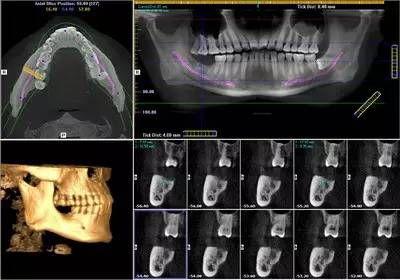

我院口腔科配備的西諾德口腔CBCT(錐形束CT),在業(yè)界被譽為神奇的“慧眼”,它能夠幫助口腔醫(yī)生詳細,清晰,了解患者口腔內(nèi)部的情況,是世界牙科聯(lián)盟指定的品牌儀器,具有當前世界先進的技術(shù)優(yōu)勢。

3.輻射劑量更低,一次CT拍攝只有29uSv,僅為普通CT的幾十分之一。

4.更高空間分辨率,對于頜面部骨骼和牙齒等硬組織的顯示比普通CT清晰約10倍。

5.影像后期處理功能強大,可以任意層厚、任意層距、任意切面,多方位、多角度的觀察病變。

6.適用范圍更廣、診斷更加,牙齒種植術(shù)前骨量及密度分析,埋伏牙的定位,牙齒矯正前的頭顱測量,復雜的根尖周病變的診斷,阻生齒拔除方案的詳細制定,頜骨囊腫范圍的確定,顳下頜關(guān)節(jié)骨質(zhì)的檢查等。

CBCT掃描可準確分析頜骨植入?yún)^(qū)的骨質(zhì)、骨量、骨密度及植體與下頜神經(jīng)管、上頜竇的關(guān)系,臨床醫(yī)生可以在圖像上模擬種植,直接與患者進行溝通及交流,并可指導手術(shù)者在手術(shù)方案中避開危險區(qū)域,手術(shù)的性。此外,臨床醫(yī)生還可以利用CT數(shù)據(jù)進行數(shù)字模型重建,配合軟件預先做好手術(shù)模板使種植手術(shù)更快捷。

眾所周知,正畸調(diào)節(jié)前對牙列的判斷是影響調(diào)節(jié)方案和終果的關(guān)鍵因素。CBCT讓我們在制訂調(diào)節(jié)方案前能清楚地評估牙根的方向及其與鄰牙的關(guān)系,大大地提高了調(diào)節(jié)方案的準確性,也避免了正畸不當導致牙根損傷的風險。